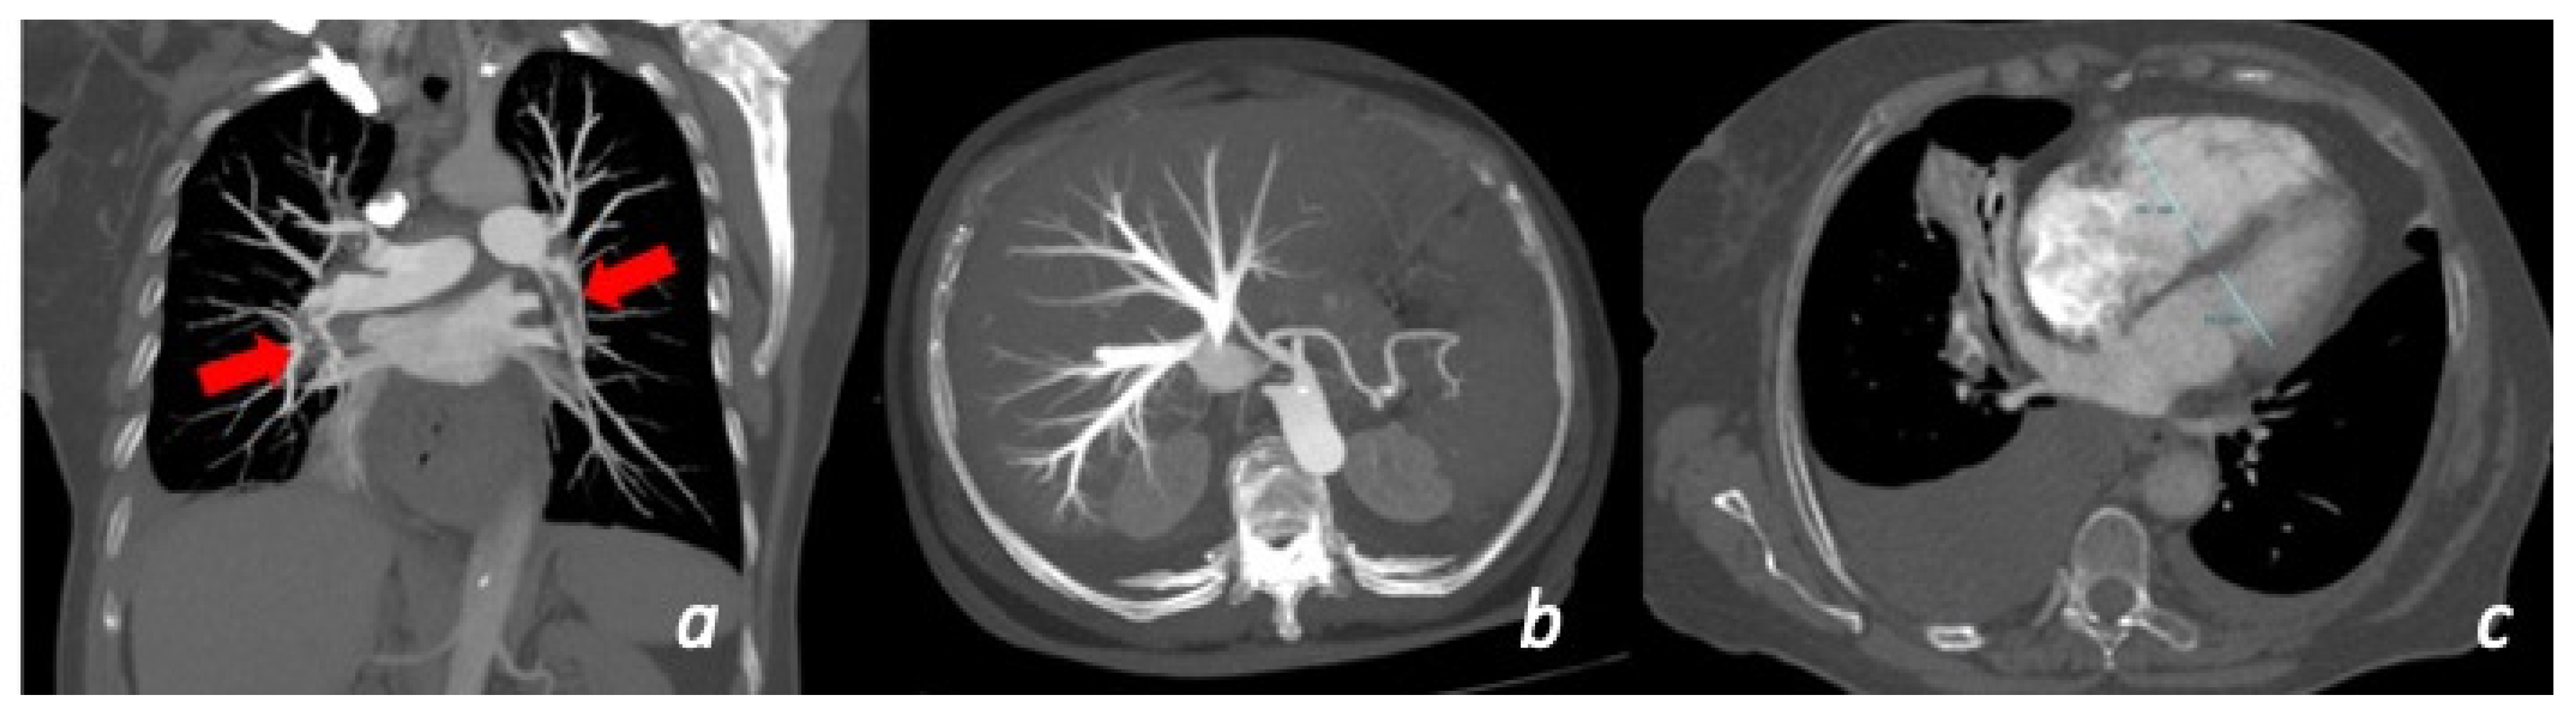

Figure 4. A 60 y/o woman presenting with acute chest pain and Troponin elevation with ECG alterations in the anterior leads. Echocardiogram showed dyskinesia of the anterior middle wall of the left ventricle. Subsequent cardiac MRI (24 h later) demonstrated dyskinetic movement in the anterior wall of the left ventricle ((a)-cine images frame in the systolic phase showing anterior bulging), associated to edema in the anterior wall (b). No LGE was found in the myocardial wall.